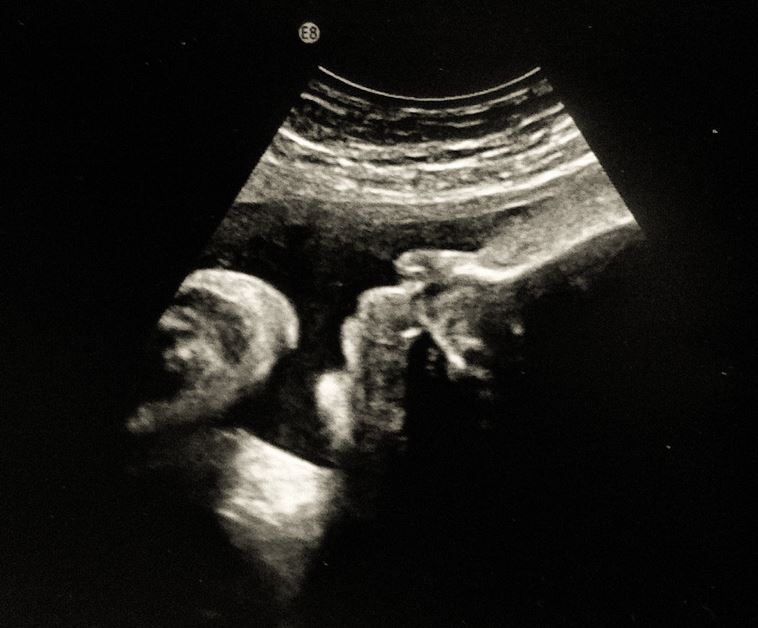

Schöne, neue Fortpflanzungswelt?

Angesicht immer ausgefeilterer Methoden der Reproduktionsmedizin stellt sich die Frage: Darf die Medizin alles, was sie kann?

Schwanger zu werden, ein Kind zu bekommen, das bedeutet heute nicht nur unvorstellbar großes Glück. Das bedeutet manchmal auch fruchtloses Warten, enttäuschte Hoffnungen und gesundheitliche Risiken. Im Gespräch mit dem „Sonntag“ fordert Martina Kronthaler, Generalsekretärin der aktion leben österreich, von der Reproduktionsmedizin verantwortungsvolleres Handeln – im Sinne der Kinder und der zukünftigen Eltern.

Anfang des Jahres gingen die Wogen hoch: Das neue Fortpflanzungsmedizingesetz wurde verabschiedet und die Reaktionen darauf waren nicht allerorts positiv. Gerade die aktion leben österreich meldete sich lautstark zu Wort. Dem neuen Gesetz fehle es an grundlegenden Dingen. Vieles werde gar nicht thematisiert, gar nicht geregelt. „Wir sehen beim Fortpflanzungsmedizingesetz viele vergebene Chancen“, sagt Martina Kronthaler, Generalsekretärin der aktion leben österreich. So sei etwa nirgendwo festgeschrieben, dass es eine umfassende Dokumentation geben muss, die zeigt, wie es Eltern und Kindern nach In-Vitro-Fertilisation gehe. Auch fehle die Vorschrift eines zentralen Spenderregisters. Nicht zuletzt sei nicht festgeschrieben, dass Kinder über die Umstände ihrer Zeugung informiert werden müssen.

Kindeswohl steht an erster Stelle

Was im Fortpflanzungsmedizingesetz aber vor allem fehle, sei der durchgehende Gedanke des Kindeswohls. „Wir müssen uns, bei all den Möglichkeiten, die die Medizin heute bietet, fragen, was wir vernünftiger- und verantwortungsbewusster Weise auch tun sollten. Was entspricht dem Kindeswohl, was tut den zukünftigen Eltern gut. Wir dürfen doch nicht alles, nur weil wir es können“, bringt es Martina Kronthaler auf den Punkt. Viele Menschen seien heute davon überzeugt, dass es ein Recht auf ein Kind gäbe. „Aber das stimmt so einfach nicht!“

Sehr kritisch sehe die aktion leben österreich vor allem all jene Methoden der Reproduktionsmedizin, bei denen die Grenzen anderer Menschen überschritten werden, wo anderen geschadet wird, die sogar ganze Familiensysteme erschüttern können – dazu gehöre vor allem die Eizellspende, in vielen Fällen auch die Samenspende. In jedem Fall aber auch die Leihmutterschaft – der „Gipfel der Instrumentalisierung von Frauen und Kindern“, wie Martina Kronthaler sagt: „Man mietet einen Körper, man kauft sich Eizellen, man kauft sich Samenzellen. Wir würden uns wirklich ein Verbot der Leihmutterschaft in der Verfassung wünschen.“ Viele Gesetze in Österreich würden hinsichtlich des Themas der Diskriminierung gleichgeschlechtlicher Paare gemacht. Aber man dürfe nicht alles nur unter diesem Blickwinkel sehen. „Natürlich sind wir auch dagegen, dass jemand diskriminiert wird“, sagt Martina Kronthaler: „Aber wenn es um Kinder geht, muss das Kindeswohl an erster Stelle gesehen werden.“

Umfassend informieren

Tatsache sei natürlich, dass die Freude über alle Kinder, die mit Hilfe der In-Vitro-Fertilisation auf die Welt gekommen sind, groß ist. „Über jedes einzelne Leben freuen wir uns“, so Martina Kronthaler. Doch müsse man auch sehen, dass oft mit der Möglichkeit, kinderlosen Paaren zu einem Kind zu verhelfen, verantwortungslos umgegangen wird. „Vielfach werden nur die positiven Seiten der IVF gezeigt – in vielen hübschen Babybildern“, sagt Martina Kronthaler. Was aber noch dahinterstehe, werde kaum kommuniziert. „Die Hormonbehandlungen sind körperlich wie seelisch sehr belastend, ganz zu schweigen vom oftmals vergeblichen Hoffen und Warten, von Fehl- und Totgeburten“, so Martina Kronthaler: „Das sind wirklich schwierige Zeiten für die Paare, eine große Belastung für die Beziehung. Es ist wichtig, dass die Paare das wissen.“

Familiengründung braucht Mut

Generell bedauert Martina Kronthaler, dass das Wissen rund um Schwangerschaft und Fruchtbarkeit in unserer Gesellschaft gar so gering ist. „Ein Kind ab 40 ist wie ein Lottosechser. Das ist in viel zu wenig Köpfen verankert.“ Die meisten seien überzeugt, dass es ab 40 schwierig werde, schwanger zu werden. Tatsächlich sei es aber so, dass die Fruchtbarkeit schon ab 30 sinke, ab 35 sogar signifikant. Davor eine Familie zu gründen, dazu fehle es aber vielen jungen Menschen an Mut. „Wenn ich Angst haben muss, meine Familie versorgen zu können, überleg ich mir dreimal, ob ich wirklich jetzt Kinder haben möchte.“ Da sei die Politik gefragt, geeignete Rahmenbedingungen zu schaffen.